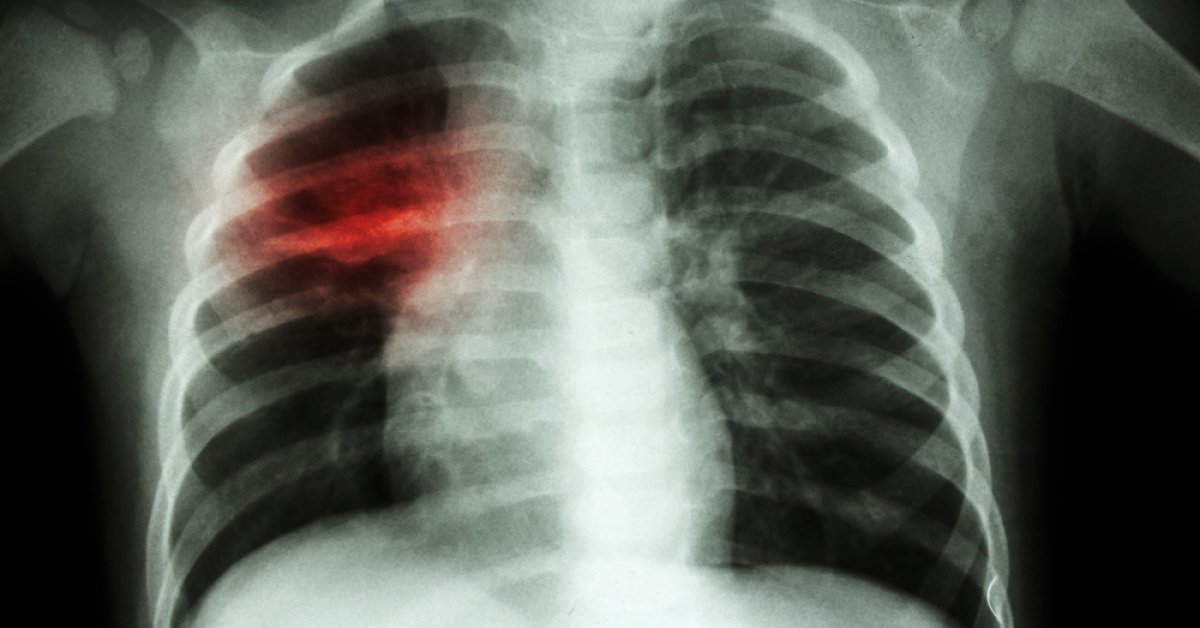

“Griptir geçer” demeyin! Zatürre tehlikesi…

Kış aylarının etkisini sürdürdüğü bu günlerde viral kaynaklı solunum yolu enfeksiyonları yaygın şekilde görülürken, poliklinik başvurularında ve hastanede yatarak tedavi edilen hasta sayısında belirgin artış yaşandığı belirtildi. “Grip oldum, geçer” düşüncesiyle hekime başvurunun geciktirilmesi ise, özellikle 65 yaş üstü ve kalp, akciğer, böbrek ya da diyabet gibi kronik rahatsızlığı bulunan kişilerde ciddi sonuçlara yol açabiliyor. […]